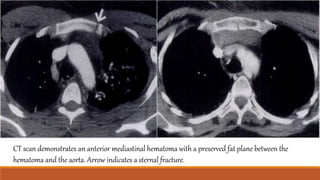

CT scan demonstrates an anterior mediastinal hematoma with a preserved fat plane between the

hematoma and the aorta. Arrow indicates a sternal fracture.